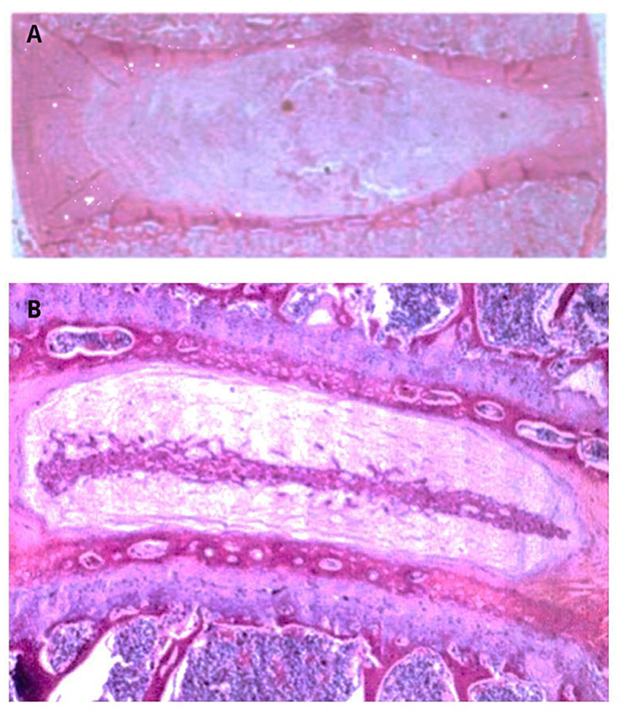

Histopathological evaluation used validated human disc scoring systems, including the Boos Histologic Degeneration Score (18), Rutges et al. classification (19), and the Orthopedic Research Society (ORS) Spine Section consensus framework (20). Degenerated discs were identified by annulus fibrosus lamellar disorganization, fissures/clefts, clustering of nucleus pulposus cells with chondrocyte-like proliferation, mucoid matrix changes, endplate irregularities, and, in some cases, neovascularization (18, 21). Control samples lacked these features. H&E was selected as the reference stain because it remains the gold standard for evaluating disc architecture and cellular morphology (1820). Representative non-degenerate and degenerate IVDs are shown in Figure 1.

Figure 1. Representative H&E stained sections of human intervertebral discs. (A) Non-degenerate control disc showing preserved AF lamellar architecture, homogeneous NP, and absence of fissures, cell clustering, neovascularization, or endplate irregularities. (B) Degenerated disc demonstrating AF lamellar disorganization, fissures/clefts, clustering of NP cells with chondrocyte-like proliferation, mucoid matrix change, and irregular endplate structure. The morphological features illustrated correspond to established histopathological criteria used in validated scoring systems for human disc degeneration (1820).